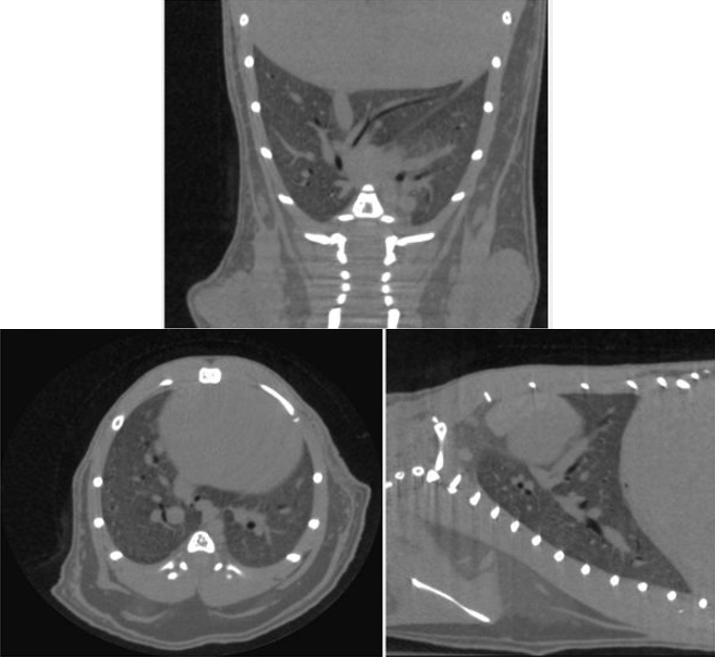

3、可变的X射线能量与一系列滤片结合,确保了无论是对肺组织还是有金属植入物的骨骼等样品的扫描,都能获取出色的图像质量,能够满足多种研究应用需求。

小鼠肺部活体扫描的正交截面成像